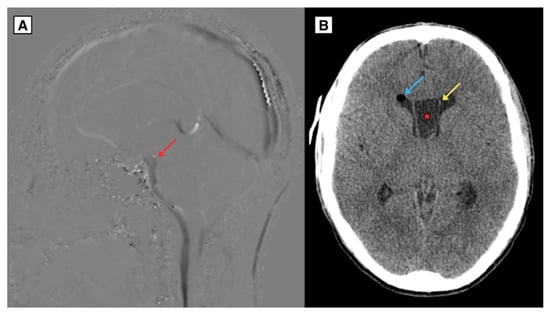

Figure 3.

MRI of the brain (A) CSF sagittal sequence (2024) of CSP and CV cysts covering the intraventricular foramen resulted in CSF flow disturbances, with almost no visible CSF flow through the cerebral aqueduct and the central spinal canal. Additionally, weakened CSF flow was noted dorsal to the medulla oblongata while increased flow was observed ventrally to the medulla oblongata. (B) CT brain scan in axial plane (2024) post endoscopic fenestration of the right side of the CSP cyst revealed brain tissue edema and air present at the surgical access site in the right frontal lobe. The CSP maximum diameter measured approximately 21.2 mm. Red arrow—interventricular foramen, Blue arrow—pneumocranium, Yellow arrow—septum pellucidum wall, Asterisk—septum pellucidum cyst.

The patient underwent neuroendoscopic fenestration of the cyst, which led to the resolution of both hydrocephalus and the symptoms. In collaboration with the Department of Neurosurgery, extensive efforts were made to retrieve and analyze the procedural images. However, due to technological limitations, it was not possible to save or export the imaging data from the procedure. A follow-up CT brain scan one day after endoscopic fenestration of the right side of the CSP cyst revealed brain tissue edema and air present at the surgical access site in the right frontal lobe.